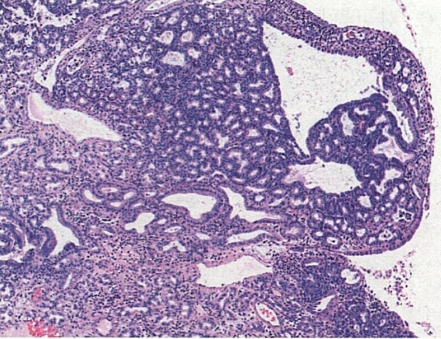

患者男,55岁。体检B超发现胆囊息肉。手术中见胆囊底部息肉样肿物,质软,切面灰红色。显微镜下观察如图所示。

1.病变最有可能弥漫强表达的免疫组织化学标志是